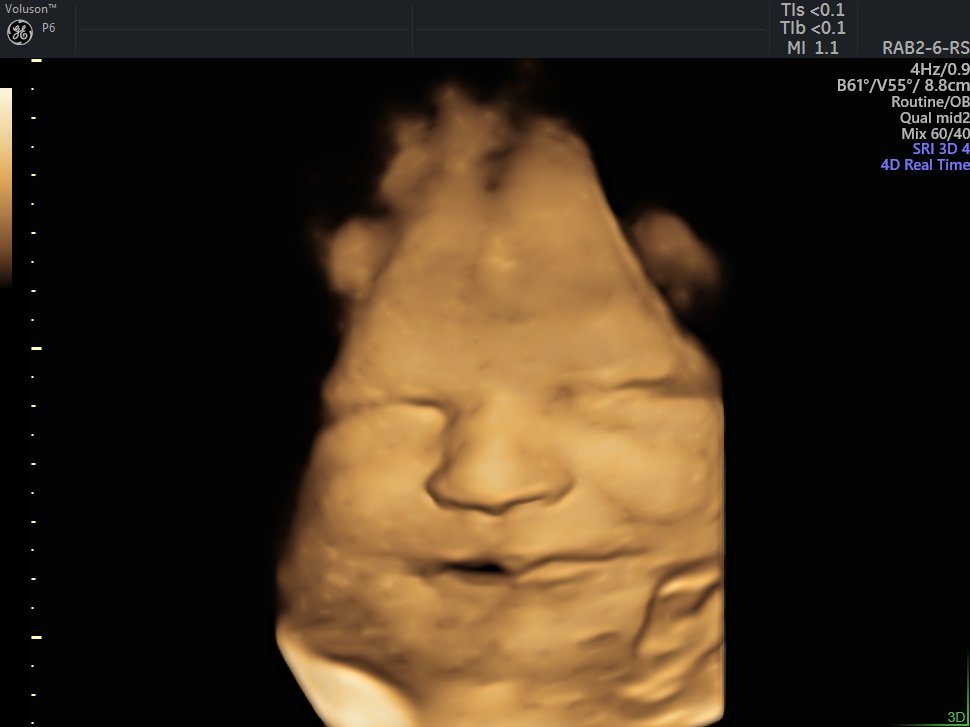

4 D Ultrasonografi

4 Boyutlu (Renkli) Ultrason ve Doppler Ultrasonografi